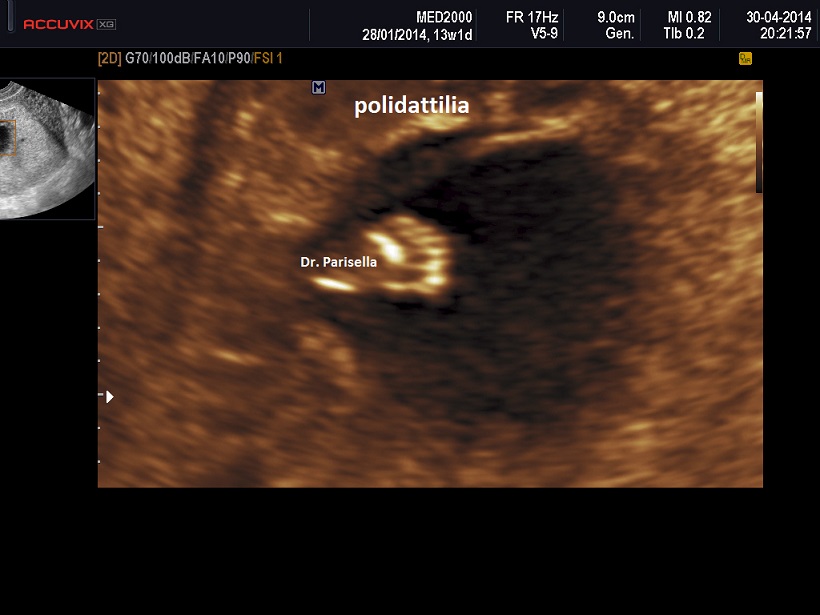

Il sospetto in diagnosi prenatale  ecografica si basa sul riscontro delle seguenti anomalie fetali:

4. polidattilia